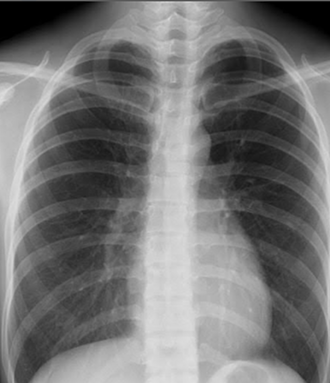

デジタルレントゲン

胸部X線肺、心臓、大血管の病気の診断に有用です。肺癌、肺結核、肺炎、肺気腫、気胸、間質性肺炎、大動脈瘤、心臓肥大等の疾患を疑うことができます。